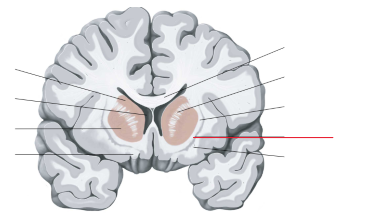

claustrum

nucleus caudatus

putamen

capsula interna (corona radiata)

laterale ventrikels (I en II)